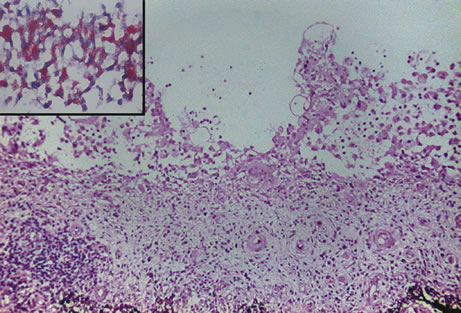

Necrotizing retinitis with secondary choroiditis is seen in protozoal infections such as toxoplasmosis or in herpetic infections. Infection with Toxoplasma gondii leads to retinitis and secondary choroiditis (Fig. 25), usually granulomatous.127 Congenital infection can be acquired in utero by transplacental transmission of the parasite from the infected mother to the fetus.128 Acquired disease occurs after ingestion of oocysts or tissue cysts.129–132 The congenital form of infection leads to atypical macular colobomas. Reactivation of the infection is caused by release of organisms that have remained dormant in the margins of old congenital retinal scars.133 The slowly proliferating form of the organism, termed the bradyzoite, can be seen in cysts. The rapidly multiplying form, termed the tachyzoite, may be difficult to identify in an infected retina or in immunocompetent individuals, but they are frequently seen in the retinitis of immunocompromised hosts.134 Active infection usually causes focal retinal opacification and an intense vitritis. These findings may give the appearance of a “headlight in a fog” in an immunocompetent person. In contrast, this clinical presentation is rare in patients with AIDS, in whom diffuse retinitis is observed with non-granulomatous choroiditis.134

Fig. 25. Toxoplasma retinochoroiditis. Necrotic retina shows cysts of toxoplasma gondii, and the choroid reveals granulomatous inflammation. (Hemotoxylin-eosin ×65.) Inset (Gomori methenamine silver ×160) shows cysts of the organisms.